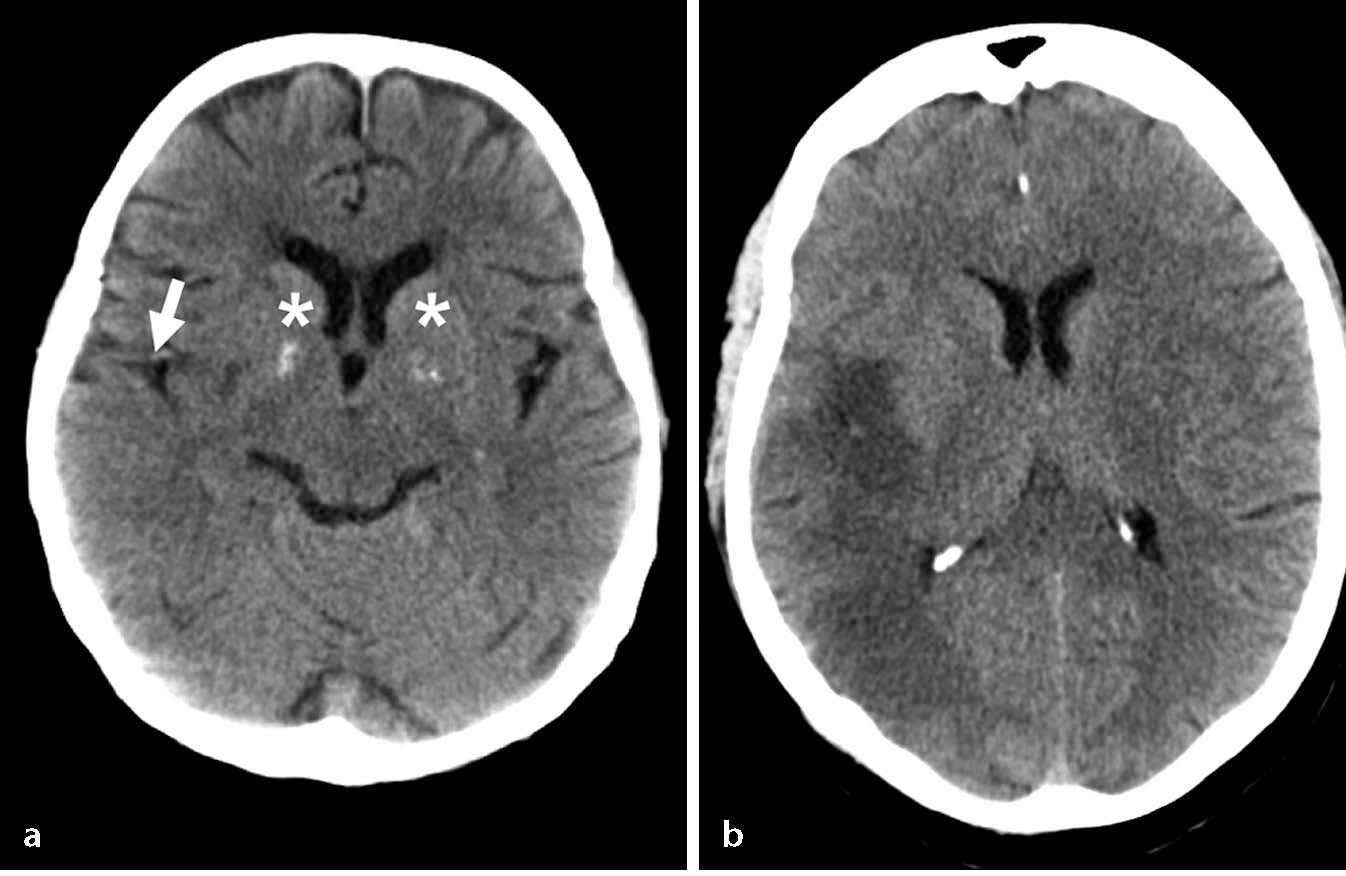

Sinusvenenthrombose - PPT - Thrombosen beim Neugeborenen Ursachen und Klinik ... - Nicht immer macht sich eine sinusvenenthrombose bemerkbar.. Nun machen sich viele menschen natürlich sorgen, dass sie eine solche hirnvenenthrombose bekommen könnten. Was sind ursachen für eine sinusvenenthrombose? Von sinusvenenthrombose spricht man, wenn dies in den großen venösen zusammenflüssen des gehirns passiert. Sinusvenenthrombose in der computertomographie ohne kontrastmittel (links) und in der kernspintomographie t1 mit kontrastmittel (rechts) beim gleichen fall. Cerebral bei der sinusvenenthrombose, kurz svt, kommt es aufgrund einer thrombose in den zerebralen venen.

Diese form ist sehr selten, kann aber tödlich enden. Was sind ursachen für eine sinusvenenthrombose? Außerdem sei dem institut in 19 fällen. Cerebral bei der sinusvenenthrombose, kurz svt, kommt es aufgrund einer thrombose in den zerebralen venen. Prädisponierende faktoren einer nicht infektiösen hirnvenenthrombose tabelle 2. Sinusvenenthrombose in der computertomographie ohne kontrastmittel (links) und in der kernspintomographie t1 mit kontrastmittel (rechts) beim gleichen fall. Was du über die thrombose im kopf und. Sechs davon hätten eine sogenannte sinusvenenthrombose gehabt, alles frauen in jüngerem bis mittlerem alter.

Bei einer sinusvenenthrombose bilden sich ein oder mehrere blutgerinnsel (thrombosen) in den großen sammelvenen des gehirns. Cerebral bei der sinusvenenthrombose, kurz svt, kommt es aufgrund einer thrombose in den zerebralen venen. Sinusvenenthrombose in der computertomographie ohne kontrastmittel (links) und in der kernspintomographie t1 mit kontrastmittel (rechts) beim gleichen fall. Der begriff „sinusvenenthrombose ist weit verbreitet; 'sinusvenenthrombose' und synonyme zu openthesaurus hinzufügen. Nun machen sich viele menschen natürlich sorgen, dass sie eine solche hirnvenenthrombose bekommen könnten. Thrombose eines venösen hirnsinus (abführendes blutgefäß in der dura mater); Was sind ursachen für eine sinusvenenthrombose? Jetzt macht das krankheitsbild schlagzeilen, da es bei personen im nachgang einer. Nicht immer macht sich eine sinusvenenthrombose bemerkbar. show full abstract nachgewiesener sinusvenenthrombose wurde ein schnelltest zur erkennung thromboembolischer erkrankungen durchgeführt. Diese form ist sehr selten, kann aber tödlich enden. Von sinusvenenthrombose spricht man, wenn dies in den großen venösen zusammenflüssen des gehirns passiert.

Sinusvenenthrombose in der computertomographie ohne kontrastmittel (links) und in der kernspintomographie t1 mit kontrastmittel (rechts) beim gleichen fall. Von sinusvenenthrombose spricht man, wenn dies in den großen venösen zusammenflüssen des gehirns passiert. Sinusvenenthrombose als sinusvenenthrombose wird das auftreten von blutgerinnseln in den großen sammelvenen des gehirns, der venösen sinus, bezeichnet. Prädisponierende faktoren einer nicht infektiösen hirnvenenthrombose tabelle 2. Bei einer sinusvenenthrombose bilden sich ein oder mehrere blutgerinnsel (thrombosen) in den großen sammelvenen des gehirns. So entsteht die thrombose im kopf | wunderweib www.wunderweib.de. Check 'sinusvenenthrombose' translations into english. Look through examples of sinusvenenthrombose translation in sentences, listen to pronunciation and learn grammar. Learn vocabulary, terms and more with flashcards, games and other study tools. Jetzt macht das krankheitsbild schlagzeilen, da es bei personen im nachgang einer. Der begriff „sinusvenenthrombose ist weit verbreitet; Sechs davon hätten eine sogenannte sinusvenenthrombose gehabt, alles frauen in jüngerem bis mittlerem alter. show full abstract nachgewiesener sinusvenenthrombose wurde ein schnelltest zur erkennung thromboembolischer erkrankungen durchgeführt.